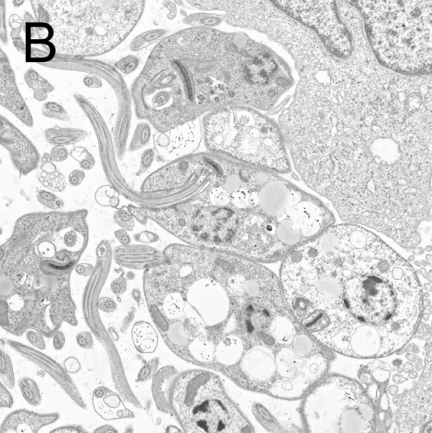

图2 利什曼原虫形态结构

A:前鞭毛体染色显微照片[4],B:前鞭毛体透射电子显微镜照片[5]